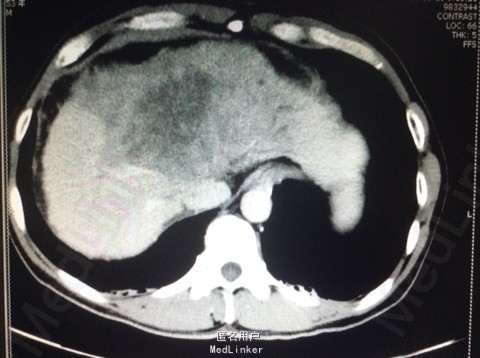

患者男,53岁。 主诉:上腹胀痛1月余。 现病史:患者于一月前无明显诱因出现上腹胀痛,为持续性胀痛,以剑突下为主,向右肩部放射,无恶心、呕吐等不适,腹痛与进食无明显关系。当地医院行CT 检查提示"肝脏右叶大片低密度影”,诊断为"肝癌可能",给予护肝等治疗,腹胀无明显好转。 起病以来,饮食欠佳,大便正常,小便色黄,体重下降3kg,体力下降。 既往史:乙型病毒性肝炎10余年。 查体:体温36.2℃,脉搏104次/分,呼吸20次/分,血压104/74mmHg,剑突下压痛,肝剑突下2横指。

辅助检查: 2013-10-16市中心医院CT提示,肝脏右叶大片低密度影 2013-10-22市中心医院胃镜1、中度食管静脉曲张,2、慢性浅表性胃炎;直肠 炎。 肝功能谷丙转氨酶22U/L,谷草转氨酶49U/L,白蛋白33.5g/L。总胆红素23.1 umo1/L,直接胆红素8.20 umo1/L。乙肝病毒(HBV-DNA) 3.13×103。 腹部超声:1.肝内巨大实质性肿块并肝左叶胆管扩张,2.肝硬化、脾肿大。

诊断:原发性肝癌(肝左叶) 处理:肿瘤细胞学性质需病理学确诊。计划给予护肝、免疫支持治疗。拟定于2013-10-31在全麻下行左半肝切除术。患者及其家属要求出院,放弃治疗。